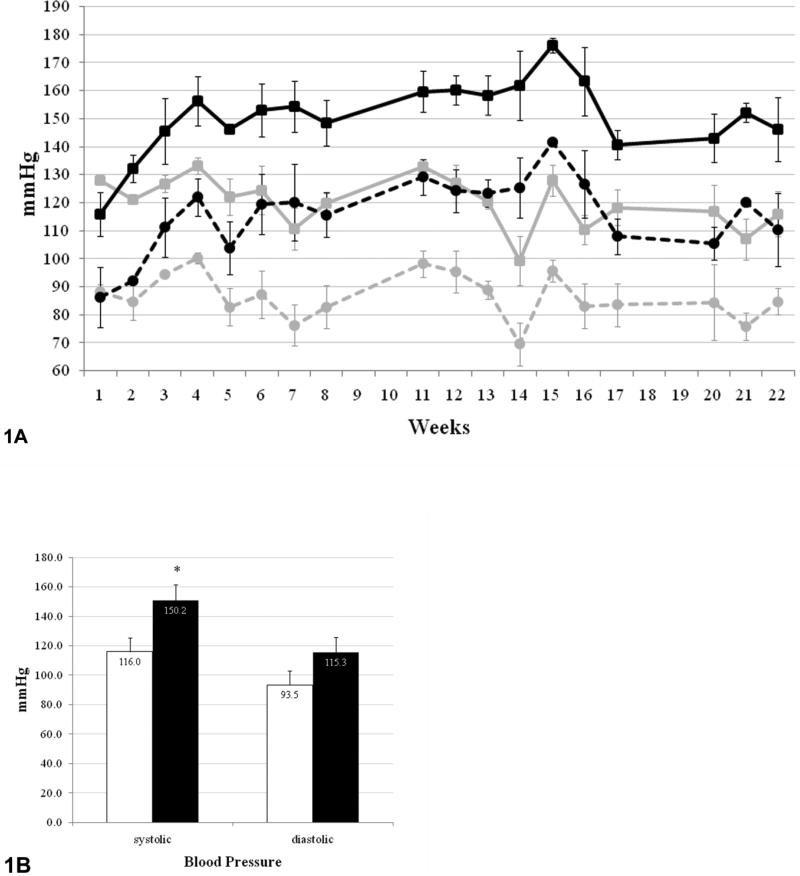

Control and arsenic exposed animals had essentially similar systolic and diastolic pressure at the start of the study (127/88 mmHg, 116/86 mmHg respectively). Systolic (squares) and diastolic (circles) blood pressure in arsenic treated animals (black lines) increased significantly and by 4 weeks of exposure, they remained above controls (gray lines) (FIGURE 1A). This hypertensive response in arsenic treated mice was maintained throughout the 22 week period. Repeated measures ANOVA was done, showing that 100 ppb arsenic exposure promoted a statistically significant increase in systolic blood pressure (p= 0.032). The change in diastolic blood pressure did not reach significance (p= 0.051), although a trend for elevated pressure was observed. Blood pressure data obtained throughout the study were averaged per treatment group (FIGURE 1B). The averaged blood pressures for control mice had normotensive values of 116/93 mmHg. In contrast, arsenic exposed mice showed significantly elevated blood pressure of 150/115 mmHg. The increase in blood pressure observed in arsenic treated animals was statistically significant for systolic values (p <0.05), but not for diastolic ones.

Figure 1. Arsenic exposure triggers hypertension.

Figure 1A. Blood pressure data shown for both control (gray) and arsenic treated (black) mice throughout the 22 week exposure. Average systolic (squares) and diastolic (circles) blood pressures are shown with respective standard deviations.

Figure 1B. Summarized averages after concluding exposure are shown for systolic and diastolic blood pressure. Control (white); arsenic treated (black). *p < 0.05.